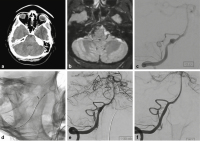

Dissektionsaneurysma

Abbildung 1a-f: Die 54-jährige Patientin erlitt bei einem Verkehrsunfall eine HWK-2-Fraktur (a, b) und eine Commotio cerebri. Das zerebrale CT zeigte in der Sylvische Fissur eine kleine umschriebene Hyperdensität (c). Angiographisch fand sich ein fusiformes Dissektionsaneurysma der rechten Arteria cerebri media (d). Das Aneurysma wurde durch zwei flusskorrigierende Stents (e, f) behandelt (p64 3,5 × 21 mm und p64 3,5 × 9 mm, Phenox, Bochum, Deutschland) und bildete sich in der Folge vollständig zurück.

Abbildung 2a-f: Die 45-jährige Patientin hatte über einige Tage Nackenschmerzen, dann Vernichtungskopfschmerz. Im CT (a) zeigte sich eine präpontine Blutansammlung. Im MRT (b) waren ältere und frischere Blutabbauprodukte nachweisbar. Die Angiographie (c) bestätigte ein fusiformes Aneurysma des rechten proximalen intraduralen V4-Segmentes mit vorgeschalteter Stenose. Ein Mikrokatheter wurde durch das Aneurysma in das distale V4-Segment eingeführt und darüber ein flusskorrigierender Stent (p64 3,5 × 21 mm, Phenox, Bochum, Deutschland) vorgebracht. Ein zweiter Mikrokatheter wurde im Aneurysma positioniert und darüber eine Coil vorbereitet (d). Während der flusskorrigierende Stent freigesetzt wurde, erhielt die Patientin die gewichtsadaptierte Initialdosis Eptifibatid (Intergrilin®, Glaxo Smith Kline, München, Deutschland) über den Führungskatheter. Gleichzeitig wurden über den zweiten Mikrokatheter Coils in das Aneurysma eingebracht und dann 500 mg Aspirin (Aspirin i.v., Bayer AG, Leverkusen, Deutschland) intravenös gegeben (e). Die intravenöse Erhaltungsdosis Eptifibatid wurde für 24h weitergeführt. Im Anschluss wurde für 12 Monate eine duale Thrombozytenaggregationshemmung mit ASS 100 mg/d und Clopidogrel 75 mg/d durchgeführt. Die Angiographiekontrolle nach einem Jahr (f) zeigte das behandelte V4-Segment mit normalem Kaliber, das Aneurysma war ausgeschaltet, es bestand kein neurologisches Defizit.